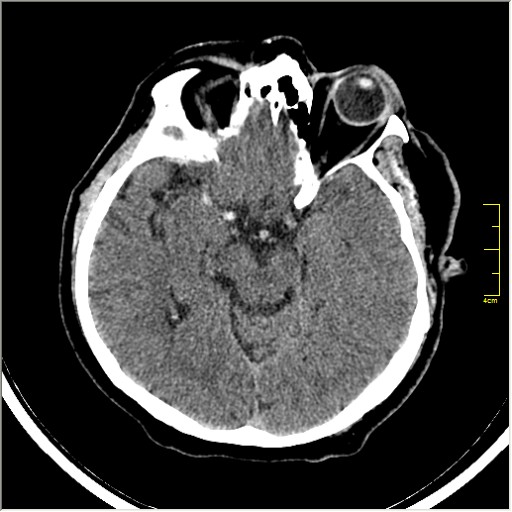

Пациентка Д. 64 года. Поступила с диагнозом ОНМК ???, жалобы на онемение и слабость в левой половине тела.

Ответ: Обратите внимание на правую среднемозговую артерию (MCA); М1 сегмент гиперденсен; сравните с другой стороной.

Этот признак называется [Dense MCA sign]; за счёт наличия тромбоза в её просвете. Этот признак является одним из ранних указующих КТ признаков при ишемическом инфаркте головного мозга. Более подробно об этом вы можете прочитать здесь: http://www.radiologyassistant.nl/en/483910a4b6f14.